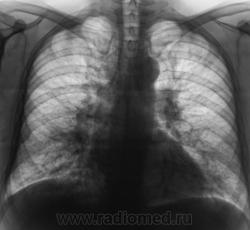

Пациент направлен на рентгенографию ОГК с диагнозом "Правостороняя пневмония". Что посоветуете коллеги?

Произведена стандартная рентгенография.

Надо понаблюдать в контроле после лечения картина на пневмонию похожа. И нужна еще левая боковая проекция там возможно тоже инфильтрат.

Сердечные проделки.

Интерстициальный отек легких. Похоже на фонге ТБЦ.

Подумал бы о саркоидозе и отправил поплевать в баночку...на фоне антибиотико терапии... и еще впечатление что идет проесс в "паракорневой" клетчатке и вообще нет литут центального процесса.. Да вот вам и диф ряд))) от сих до сих...

Наши клиницисты поставили "Пневмонию" (о рентгенологическом заключении умалчиваю) и назначили массивную противовоспалительную терапию.